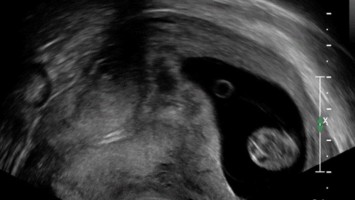

Simultane intra- und extrauterine Gravidität

Bei einer 37-Jährigen wurde eine IVF und ein Transfer mit zwei Embryonen durchgeführt. Einen Monat später treten starke Bauchschmerzen auf. Im Ultraschall zeigt sich: sowohl intrauterin als auch in der Tube rechts kann eine Fruchthöhle dargestellt werden. Was kann getan werden, um das Leben der Patientin und die intrauterine Schwangerschaft zu retten?